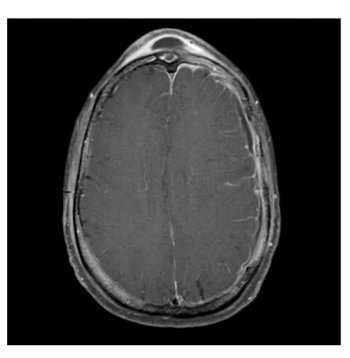

A rare case of Pott puffy tumor occurs in an atypical patient with no risk factors, likely due to untreated sinus infection.